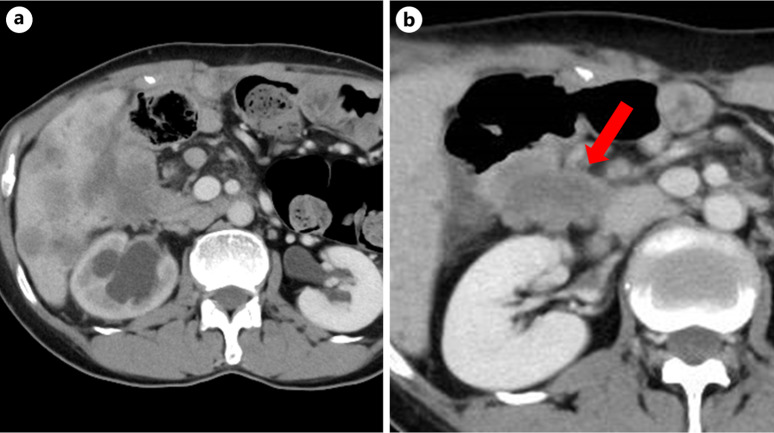

Case presentation: A 52-year-old woman was referred for a duodenal polyp. Endoscopy revealed multiple duodenal bulb polyps suggestive of Brunner's gland hyperplasia. Histopathology confirmed well-differentiated tubular adenocarcinoma with submucosal invasion and a positive margin. The patient underwent pancreaticoduodenectomy, and residual subserosal carcinoma was detected. Despite adjuvant chemotherapy, liver metastases and peritoneal dissemination developed 7 months postoperatively. The patient died 24 months after surgery.